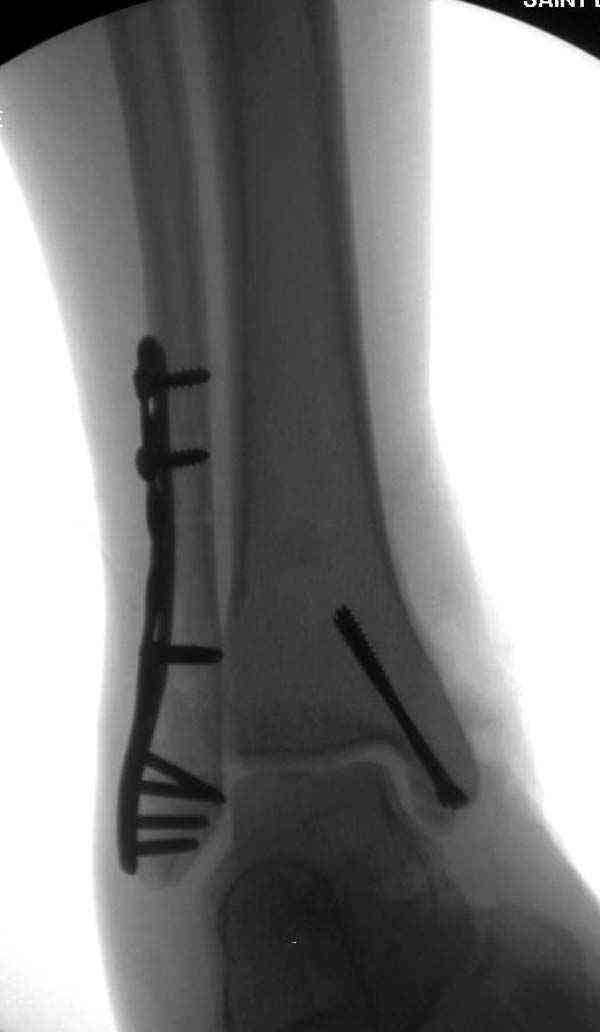

Описанная вами техника "Внутренняя лодыжка фиксирована по Веберу, наружная реконструктивной пластиной с наложением болта-стяжки" существует, но этот подход морально устарел, и применяется очень редко, только при отсутствии имплантов.

Реконструкционные пластины на лодыжке очень грубые, и из-за тонкого слоя кожи над дистальным концом малоберцовой могут осложниться пролежнями кожи изнутри.

Нет первичных снимков, перелом очень низкий и под большим сомнением диагноз разрыва синдесмоза. Медиальная сторона отрепонирована на "хорошо" и, по-видимому, прорезание проволоки произошло во время операции. Без снимков трудно судить о высоте малоберцовой, а лодыжка находится в варусе. Лагирование получилось, но возле тонких шурупов передне-задний шуруп выглядит немного тяжеловато.

Во всех руководствах АО имеется описание техники применения низкопрофильных пластин 1/3 трубки, которые могут быть применены для фиксации наружной лодыжки. Фиксацию проводят кортикальными 3.5 мм шурупами, и если дистальная фиксация недостаточная, тогда усиливают конструкцию созданием hook plate. Сгибая конец пластины на последнем отверстии, внедряют его в дистальный отдел, и тем самым создается дополнительная фиксация.

Современные преконтурированные пластины не имеют таких недостатков, и разделяются на правые и левые, а также на латеральные и задние. Множественные дистальные шурупы 2.7 мм уменьшают подкожное раздражение, и такой имплант можно оставить на долгий срок без удаления.

Для молодых достаточным бывает обычная лодыжечная пластина без блокировки, и только у пожилых с остеопорозом лучше взять полиаксиальные пластины с угловой стабильностью.

Здесь несколько частных случаев: перелом голеностопа со сравнительными снимками и разрыв синдесмоза, а также медиальная Hook пластина.